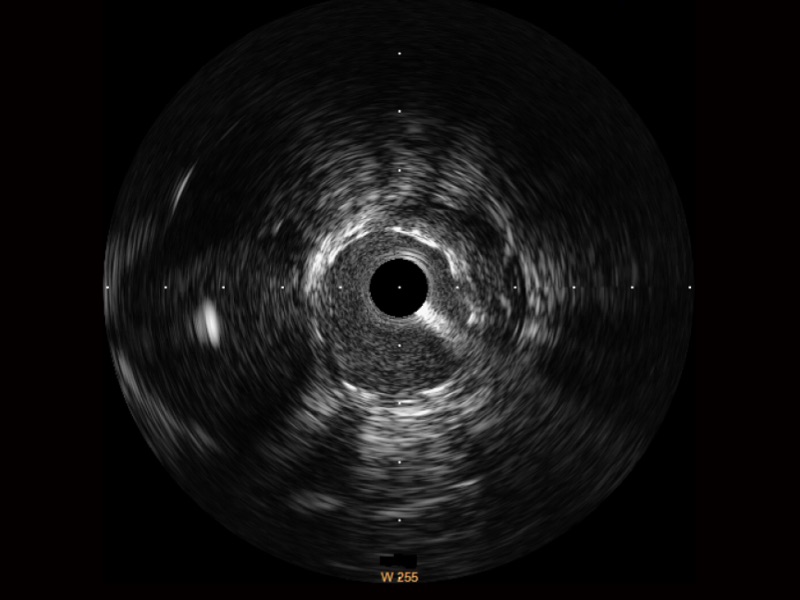

云顶集团官网宽频IVUS图像

对比传统IVUS导管成像,云顶集团官网宽频IVUS图像的近场支架梁显影更细腻,远场中膜外血管仍清晰可辨,兼顾远中近,兼顾分辨力与穿透深度